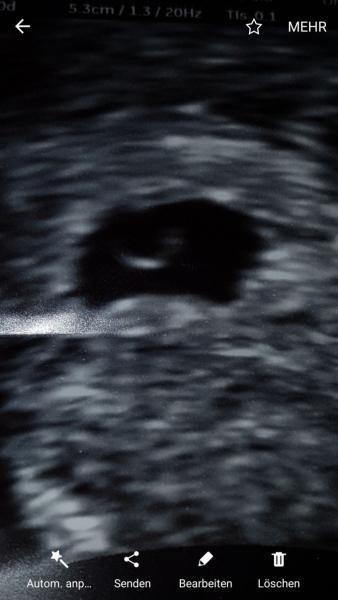

Hallo ihr lieben, mich beschäftigt mein Ultraschallbild. Habe die beiden Stellen mit Pfeilen markiert. Ich bin rechnerisch bei diesem bild Anfang 7ssw gewesen. Vom Arzt eine Woche zurückdatiert, also 6ssw. Ebenso laut ihm leere FH und verdacht auf Windei. Zumal bei HCG am tag dieses Bildes nur 2900 betrug und 2 Tage später auf nur 3200 angestiegen war. Aber was sind das für komische Stellen in der FH? Oder ist es was unbedeutendes? Was meint ihr ? Und sah es ssw, ultraschall und hcg wert technisch vielleicht bei jemandem ähnlich aus? Ich danke euch fürs lesen! Liebe Grüße

Huhu ich meine die stellen am Rand der FH. Habs dir hier mal vergrößert.